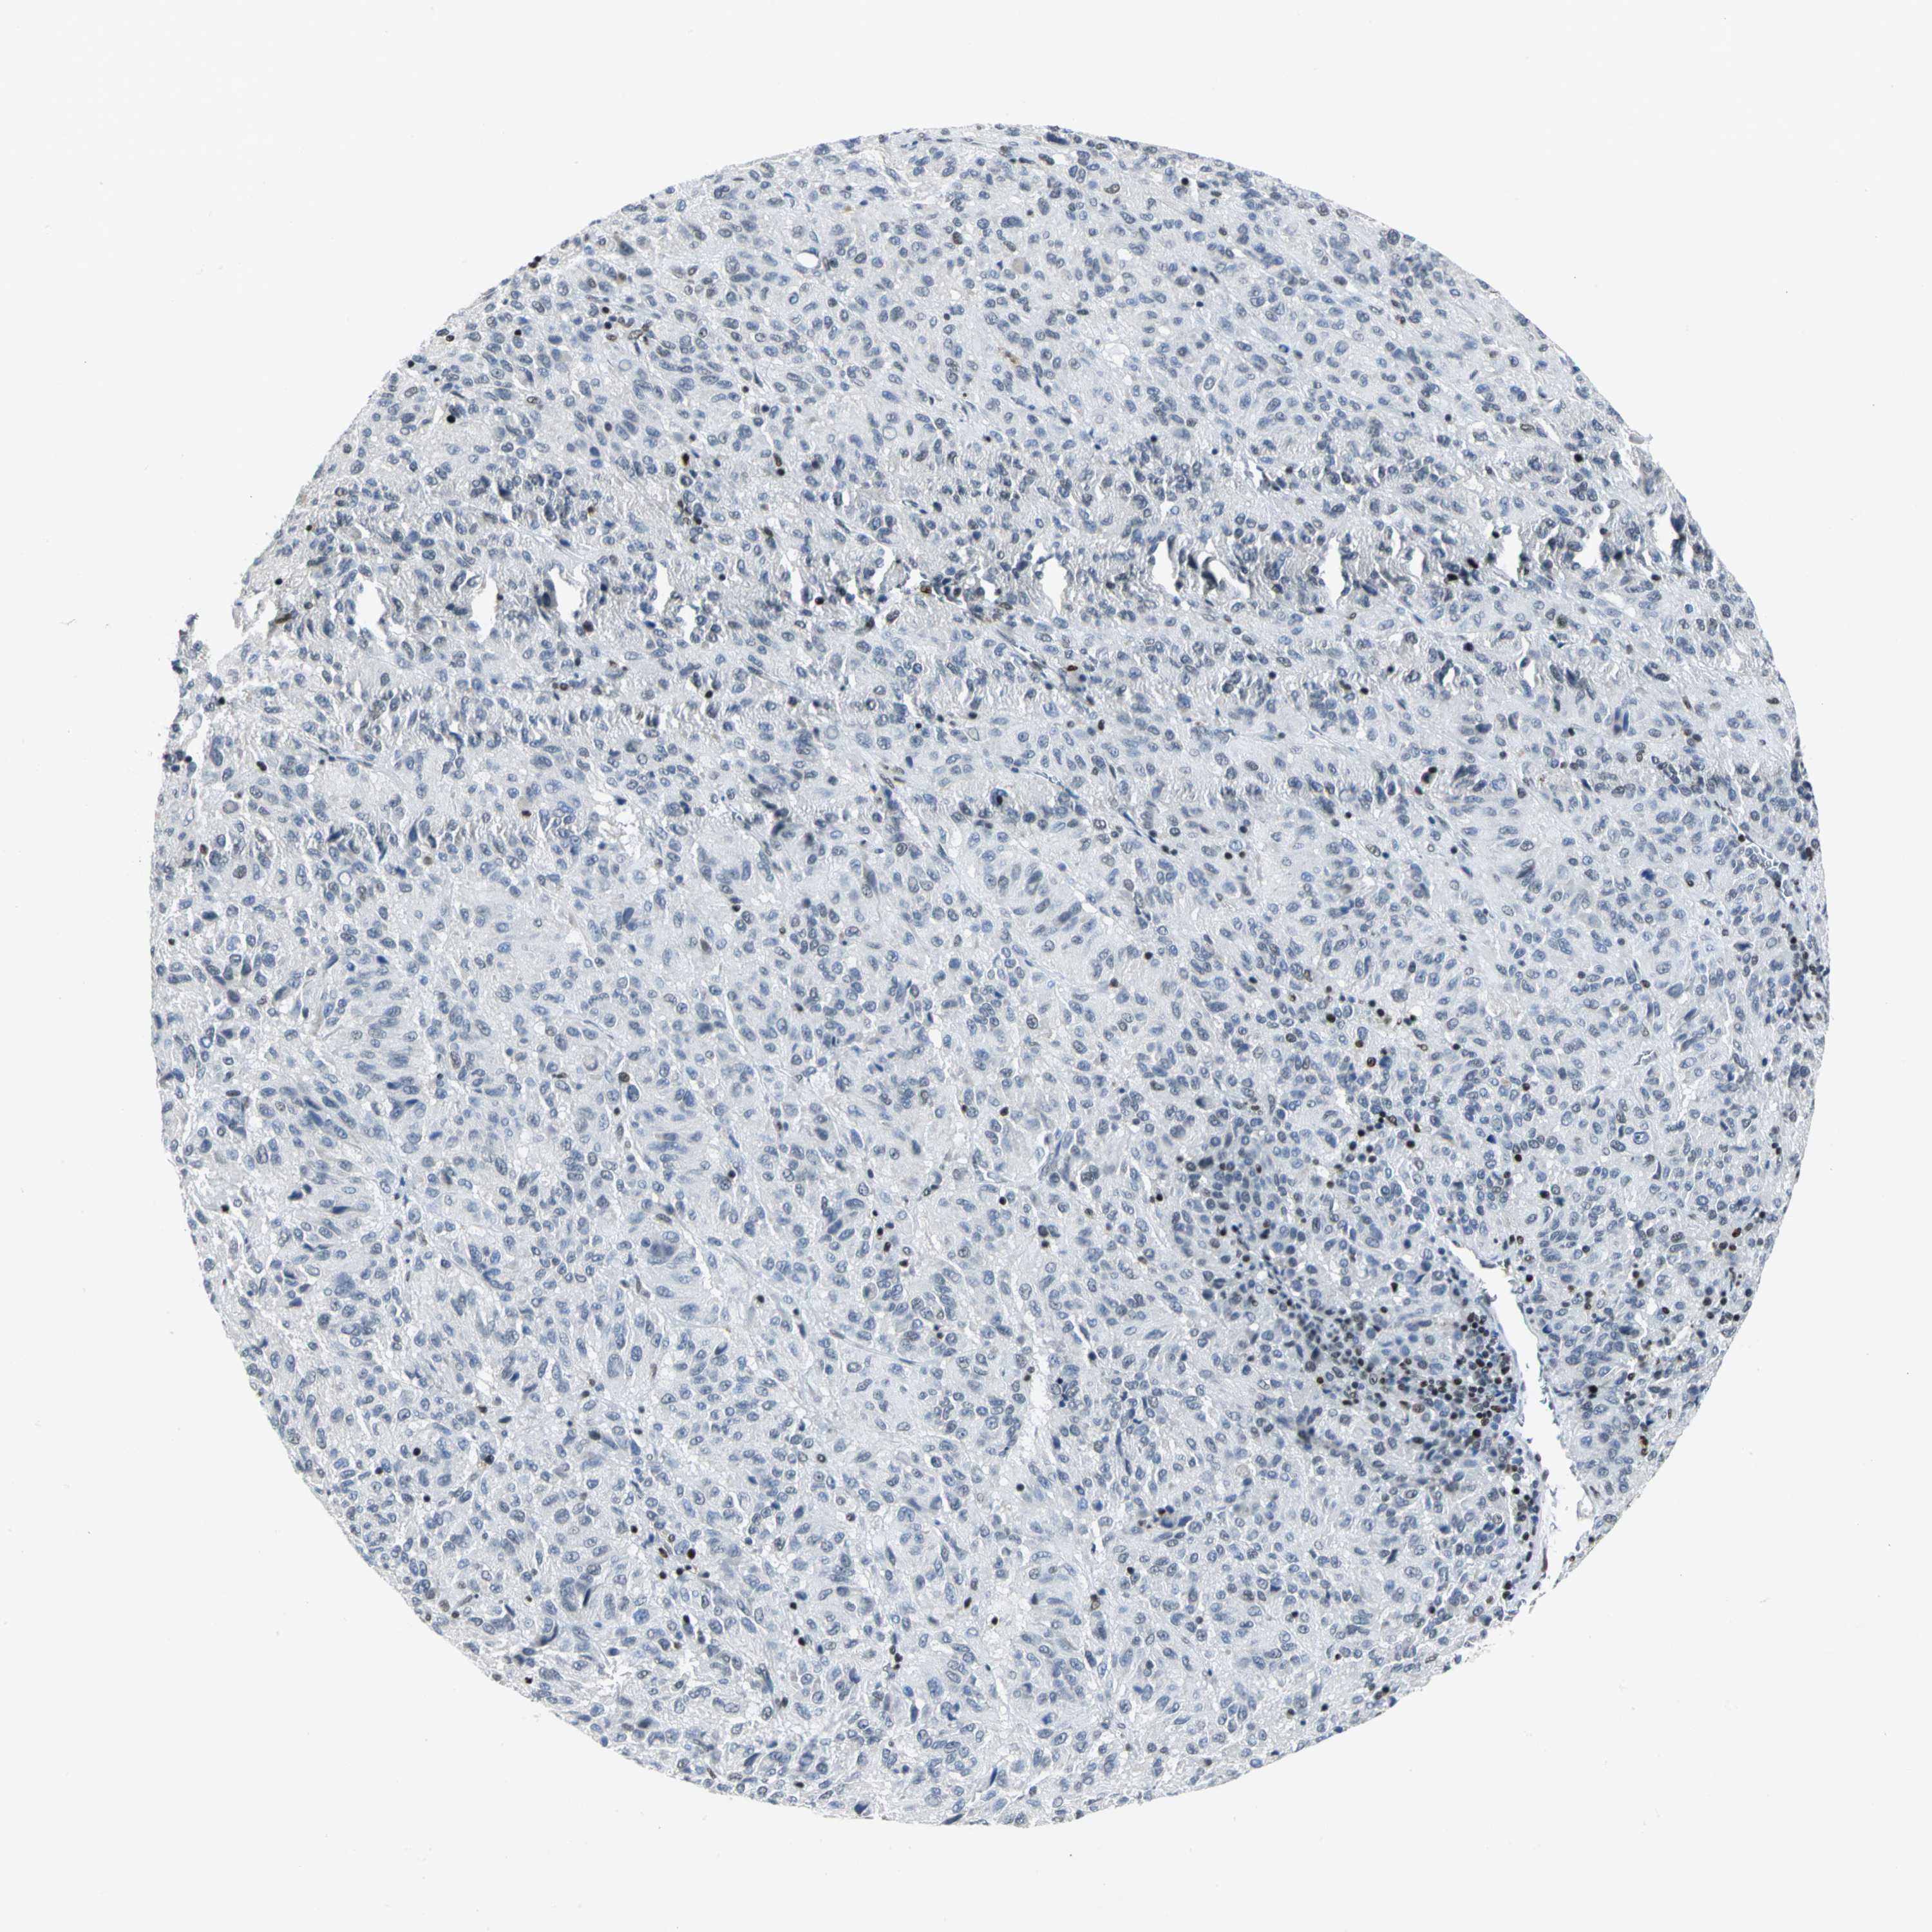

MELANOMA - Protein expressioni

A mouse-over function shows sample information and annotation data. Click on an image to view it in a full screen mode. Samples can be filtered based on level of antibody staining by selecting one or several of the following categories: high, medium, low and not detected. The assay and annotation is described here.

Note that samples used for immunohistochemistry by the Human Protein Atlas do not correspond to samples in the TCGA dataset.

Antibody stainingi

Antibody staining in the annotated cell types in the current human tissue is reported as not detected, low, medium, or high, based on conventional immunohistochemistry profiling in selected tissues. This score is based on the combination of the staining intensity and fraction of stained cells.

Each image is clickable and will lead to virtual microscopy that enables deeper exploration of all samples and also displays staining intensity scores, fraction scores and subcellular localization as well as patient and tissue information for each sample.

Antibody HPA004911

Staining

High

Medium

Low

Not detected

Intensity

Strong

Moderate

Weak

Negative

Quantity

>75%

75%-25%

<25%

None

Location

Nuclear

Cytoplasmic/membranous

Cytoplasmic/membranous,nuclear

Malignant melanoma, NOS

Malignant melanoma, Metastatic site